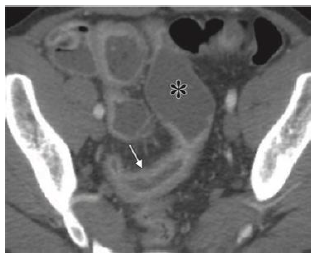

Homem de 29 anos de idade, tabagista, com emagrecimento significativo, dor no quadrante inferior direito do abdome e diarreia recorrentes, admitido no Pronto Atendimento em mal estado geral, 5 evacuações líquidas por dia, febre de 38,2ºC, dor intensa no quadrante inferior direito do abdome, anemia importante, leucocitose, proteína C reativa e calprotectina fecal aumentadas. Além disso, o exame físico revelou lesões compatíveis com eritema nodoso em membros inferiores.

A Figura 1 é representativa dos achados da tomografia computadorizada do abdome realizada na urgência.

Figura 1. Fonte: RadioGraphics 2018; 38:1352–1369